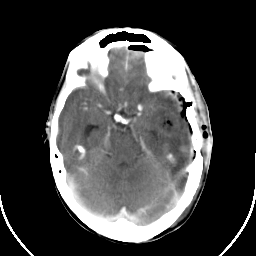

Metastatic bronchogenic carcinoma: Roentgen-ray CT (post-op) -- Slice #7

[Home][Help][Clinical] Slice 7